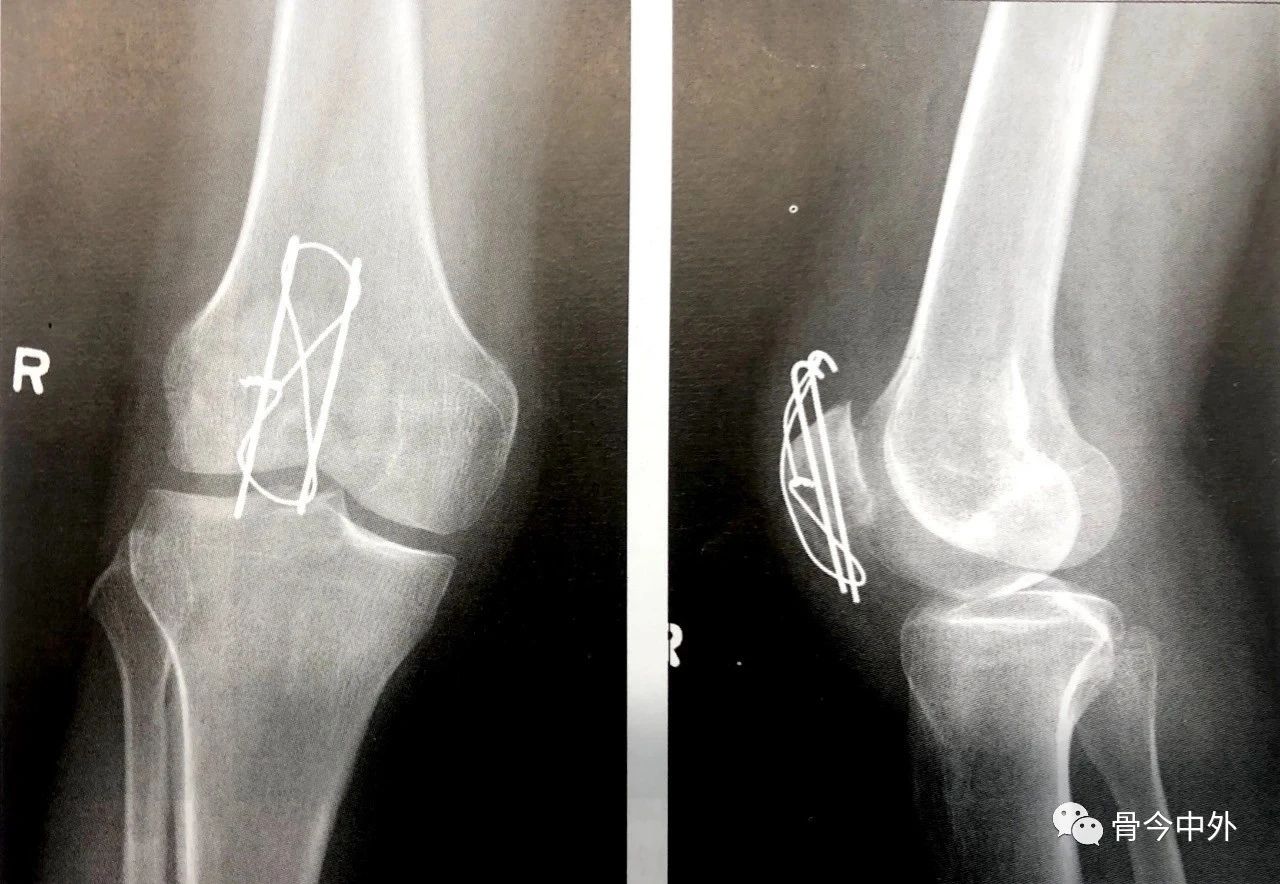

- 克氏针或螺丝钉应在髌骨前皮质面下大约5mm打入,在骨质内冠状面和矢状面上相互平行(图6A)。

- 在穿过骨折线之前,可用术中透视(正位和侧位)直视下或将手指伸到髌骨下触摸的方式来确保骨折已复位。

- 使用14或16号的导管作为环扎线的通道。将其穿过临近骨质的四头肌腱和髌韧带内以尽量减少由钢丝所致的软组织损伤(图6B)。

- 钢丝尽可能接近髌骨,这一点很重要。

- 然后以导管作为通道将18号钢丝穿入软组织内。

- 钢丝的两端在髌骨前面呈8字形交叉(图6C)。

- 张力带也可打成非交叉的方式。

2.在直视,触摸或同时借助于术中透视的方式下确保髌骨的关节面达到充分复位,这点非常重要。

图6